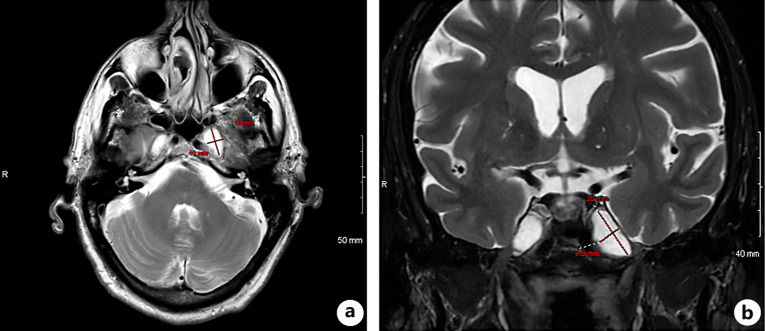

Case presentation: A 74-year-old male presented with acute onset headache, vision changes, and gait instability. His medical history included hypertension and melanoma. Examination revealed a left cranial nerve VI palsy. Initial imaging with head CT and CTA showed no acute intracranial abnormalities but revealed moderate chronic sinusitis. Magnetic resonance imaging demonstrated large bilateral Meckel's cave cephaloceles, more prominent on the left, with mass effect on the inferior margins of the cavernous sinus. Steroid treatment was initiated for suspected influenza-associated cranial neuropathy. Follow-up did not reveal an immediate improvement. However, after several weeks of steroid treatment, his symptoms improved significantly. The patient deferred surgical intervention.